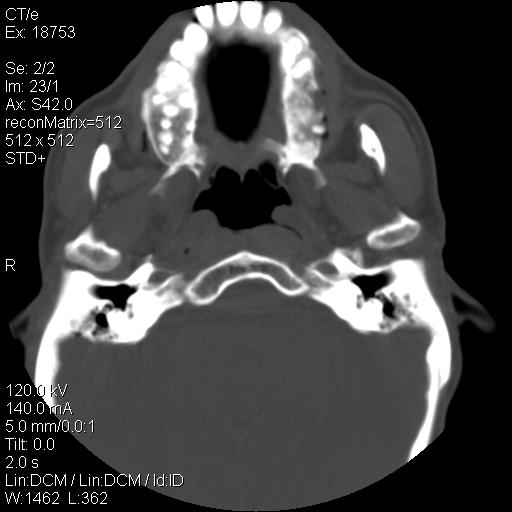

标题: CT21693:男 58岁 右侧咽部疼她2天余 PE:右侧扁桃体肿大 压痛 [打印本页]

标题: CT21693:男 58岁 右侧咽部疼她2天余 PE:右侧扁桃体肿大 压痛

右化脓性扁桃体炎症伴咽后壁脓肿形成.

1 弥漫性肿胀,与周围组织分界清晰,发病急,有明显症状,考虑急性炎症【wbc]

弥漫性肿胀,与周围组织分界不清,发病急,有明显症状,考虑:感染性病变!

结合病史,考虑感染性病变;建议抗炎治疗复查排除肿瘤性病变。